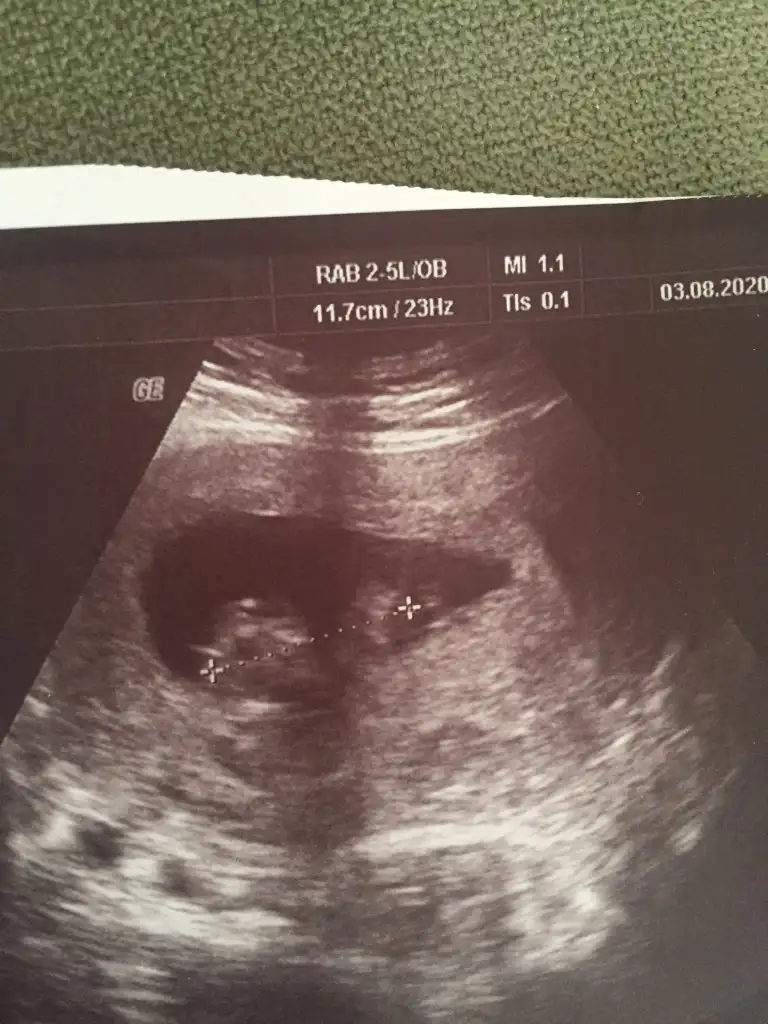

Yaa çıkıntı yukarı doğrumu sizce

Bence evet ama 11 12 13 haftalar gerekliYaa çıkıntı yukarı doğrumu sizce